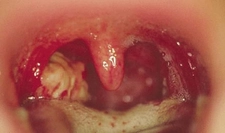

Bademciğe Ne İyi Gelir?Bademcikler, boğazın arka kısmında bulunan ve bağışıklık sisteminin bir parçası olan lenfatik dokulardır. Genellikle enfeksiyonlara karşı savunma mekanizması olarak görev yaparlar. Ancak zaman zaman bademciklerde iltihaplanma ve enfeksiyon görülebilmektedir. Bu durum bademcik iltihabı (tonsillit) olarak adlandırılır. Bademciğe iyi gelen bitkiler ve doğal yöntemler, bu rahatsızlığın tedavisinde yardımcı olabilir. Bademciği Rahatsız Eden BelirtilerBademcik iltihabının başlıca belirtileri şunlardır: